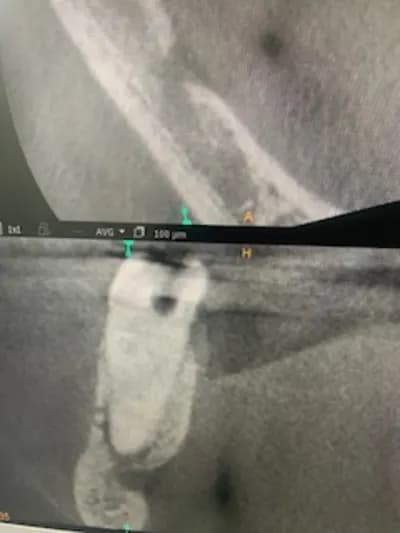

Une 3d se regarde dans le mouvement, comme une échographie.

Ce mouvement permet de voir que le ndi se divise en deux avec deux foramina, un lingual et un vestibulaire.

Je ne pense donc pas que ça soit l’artère sub linguale.

Sur le cas de ce jour la 3D laisse apparaitre la seconde paire de foramen sur NAI